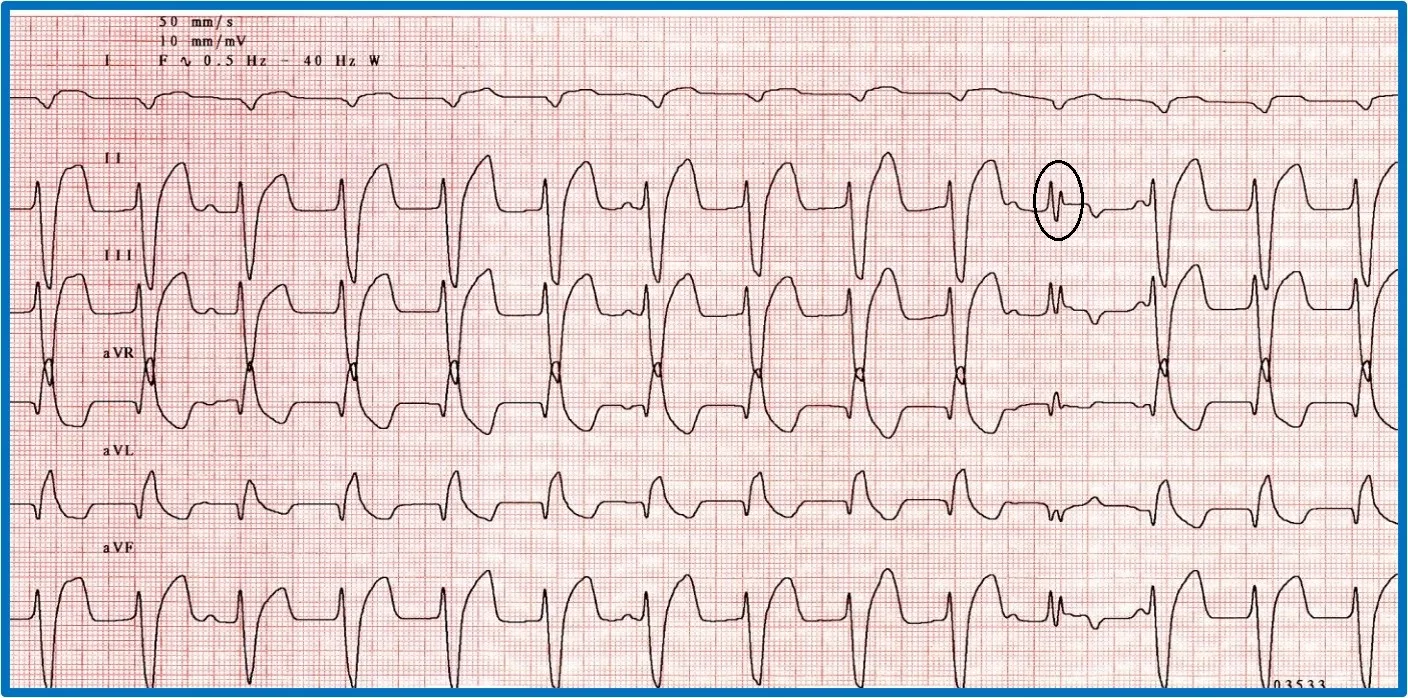

Premature beats originating at or above the AV junction can still be rapidly conducted to the ventricular myocardium via specialized conduction tissue and therefore appear nearly identical to the regular rhythm. Premature beats originating below the AV junction (ie, below the bundle of His) cannot use the specialized conduction system and must therefore depolarize the ventricles via muscle cell to muscle cell conduction. This is a relatively slow process that produces a wide, bizarre QRS complex that can be predominantly positive or negative depending on where and in which ventricle the impulse starts and what direction it travels from to allow for complete ventricular depolarization. There will not be a related P wave because the impulse forms and depolarizes independently from atrial depolarization. Because depolarization is abnormal, repolarization is also abnormal and is represented by a large, bizarre T wave on ECG (Figure 6).

FIGURE 6 Effect of ectopic foci origination location on ECG appearance. (A) ECG showing a normal QRS complex but indiscernible P wave (circle) characteristic of premature beats with supraventricular origin; the circled premature beat is almost identical to the beats with an associated P wave. (B) Illustration demonstrating where ectopic foci result in supraventricular (above dotted line) and ventricular (below dotted line) ECG patterns. (C) ECG showing no P wave; a wide, bizarre QRS complex; and a large, bizarre T wave (circles) characteristic of premature beats with a ventricular origin.

Two versions of ventricular runs of ectopy. (A) ECG showing a run of sustained true VT with a rate of 320 bpm in a boxer. (B) ECG showing an AIVR rhythm (ie, slow VT) in a crossbreed dog hit by a car and experiencing traumatic myocarditis. The rate is 180 bpm and not hemodynamically compromising the patient. A sinus beat occuring at the same time as a ventricular beat, causing a fusion beat (circle), can be seen.